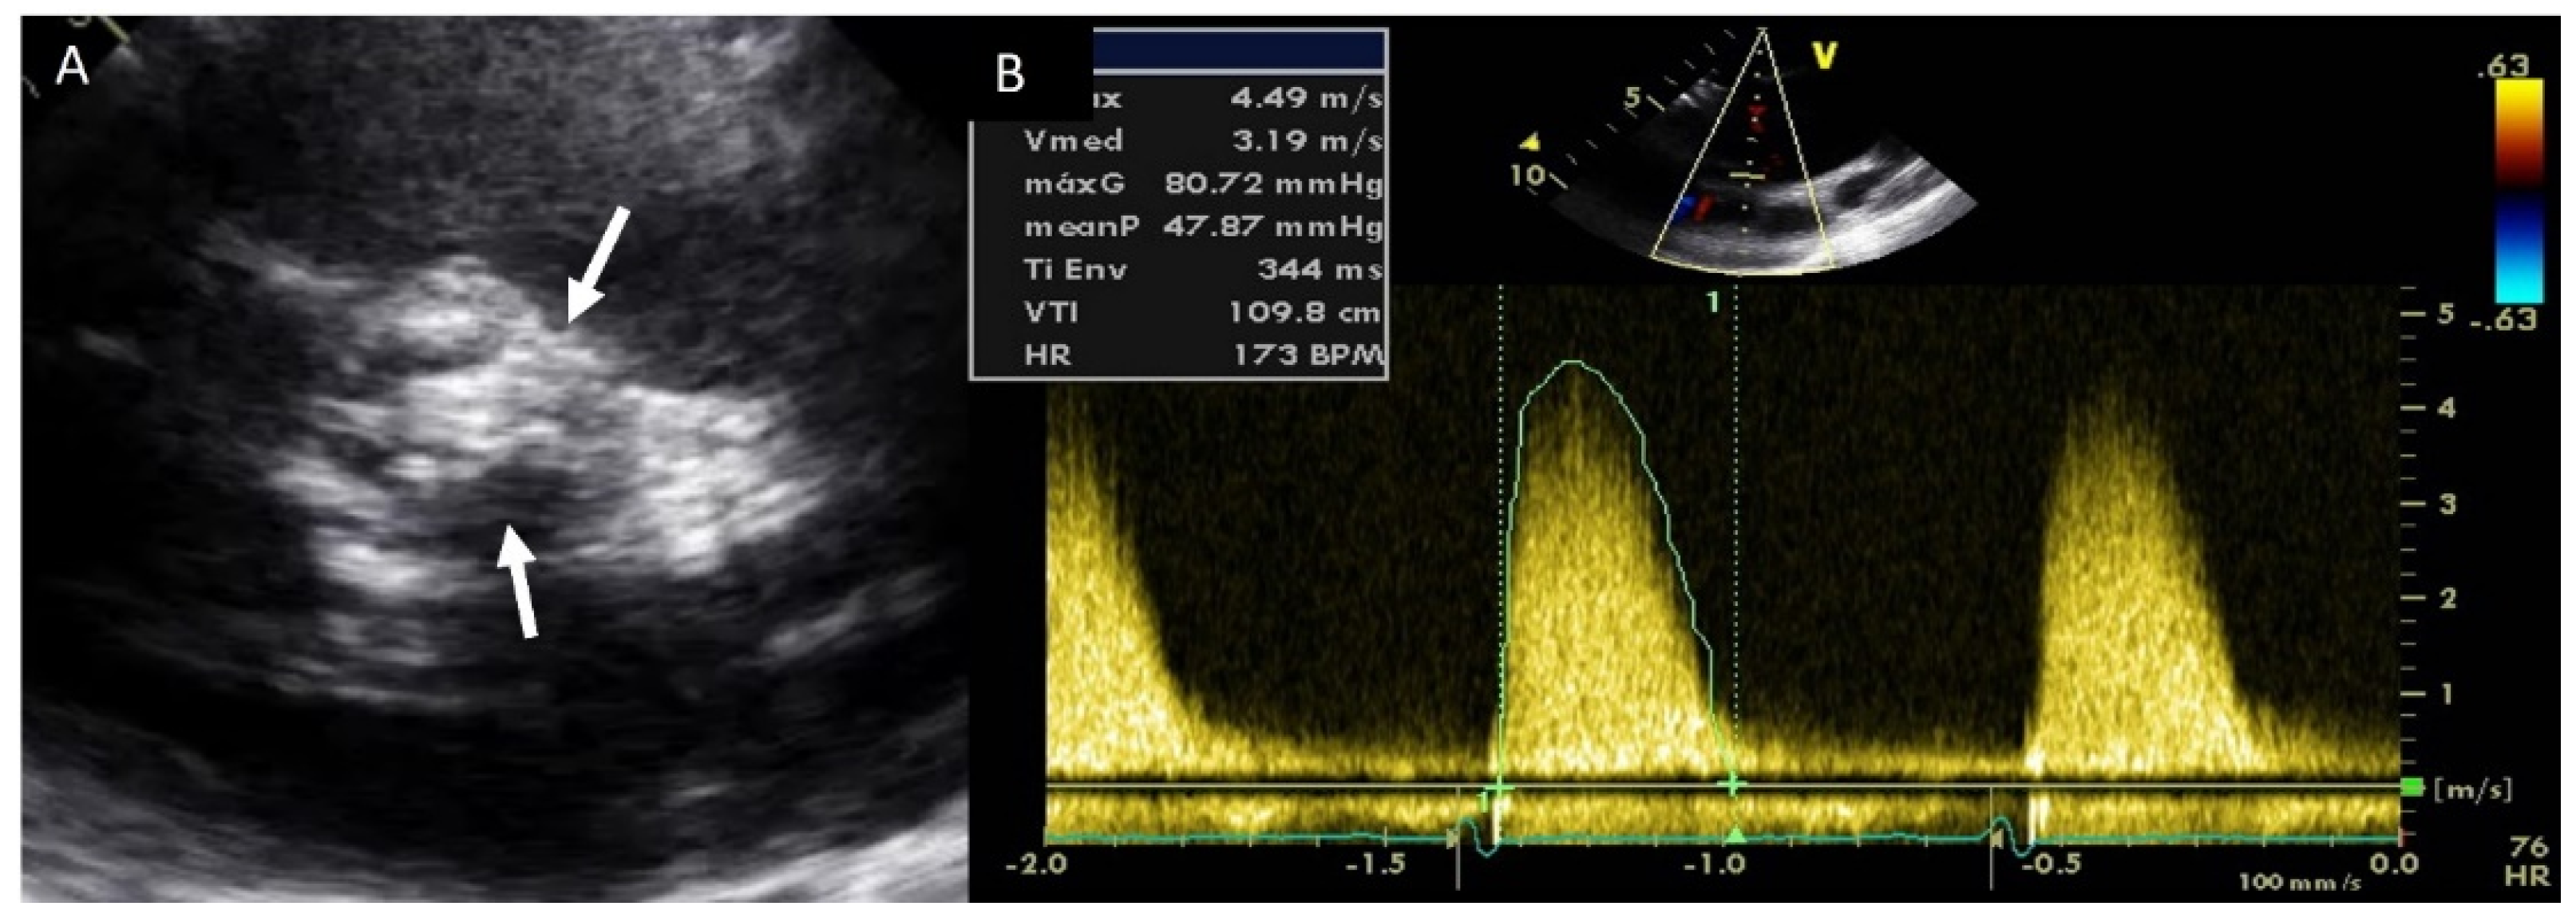

4.2. Aortic Stenosis

4.3. Aortic Regurgitation